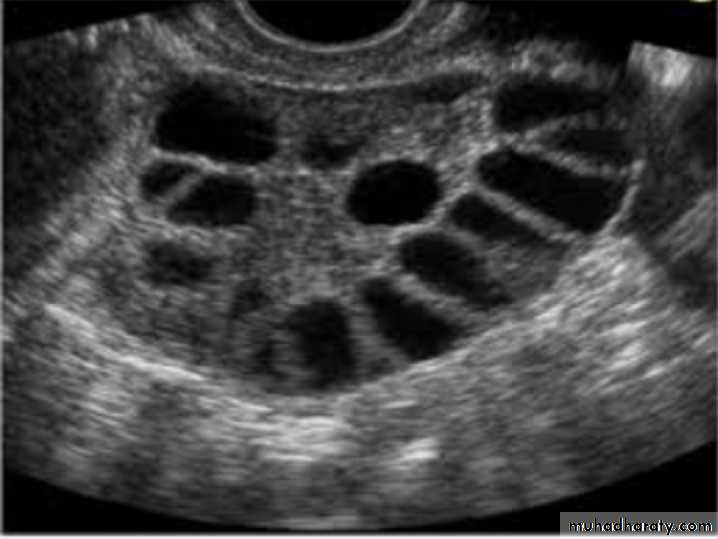

Pt. present with irregular vaginal bleeding , what is Dx? PCOS

Typical U/S finding in this case : bilateral ovaries containing multiple follicle more than 10 measure 2-9 mm diameter arranged in a neglict apperance with increase stromal thick and overian volum (>10cm3)

What other symptoms: 1-hisutims 2-infertility 3-obesity 4-acne 5-amenorrhea or oligomenorrhea

Lab. Finding :Increase serum LH

Increase serum LH : FSH ratio

Increase serum androgen (testosterone and androstenedione)

Decrease SHBG

Increase estradiol and estrone (not measured routinely as Very wide rang of values).

Increase serum prolactin.

Increase serum insulin level.

Impaired glucose tolerance .

U/S:PCOS